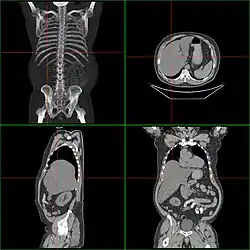

Computerized tomography of affected person with hepatomegaly | |

Computerized tomography (CT) can give accurate anatomical information for a complete diagnosis.[22]